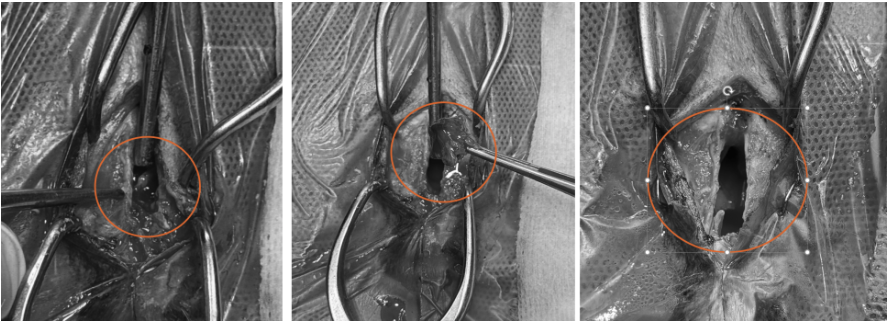

콧등뼈 절제 후 확인되는 종양(좌) / 종양을 비강에서 꺼내는 모습(가운데) / 종양 절제 후 깨끗해진 비강내부(우) / 출처: 에스동무레디컬센커 울산점